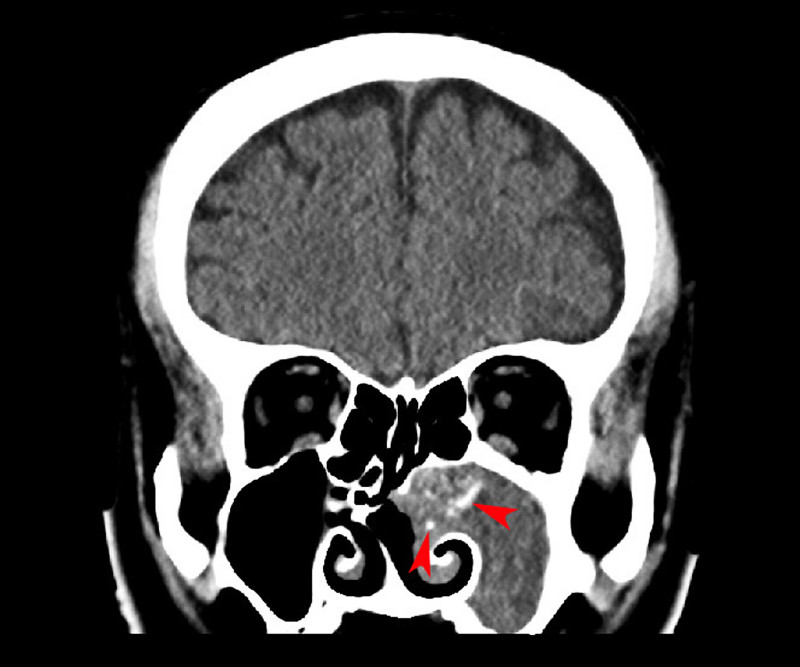

56歲的林小姐半年來飽受鼻塞、咳嗽有痰偶爾帶血絲,服用多輪抗生素治療未改善,經轉介前來就醫,內視鏡檢查確認是鼻竇炎問題,結合電腦斷層檢查發現,引起鼻竇炎的罪魁禍首不是細菌,而是感染了黴菌!(圖1)黴菌在她的鼻竇裡堆積成黏土狀(圖2),即使鼻沖洗也難以清除,須手術打開鼻竇、完整移除黴菌塊,手術後她不需使用抗黴菌藥物即可順利康復,也終於放下心中的大石。

黴菌球不是腫瘤,不會侵蝕鼻竇,但會在鼻竇中逐漸堆積、乾燥凝結,形成一團像黏土般的硬塊,無法自行排出。黴菌球內常有鈣化,影像學檢查上會呈現亮白如石頭般的特徵(圖3)。